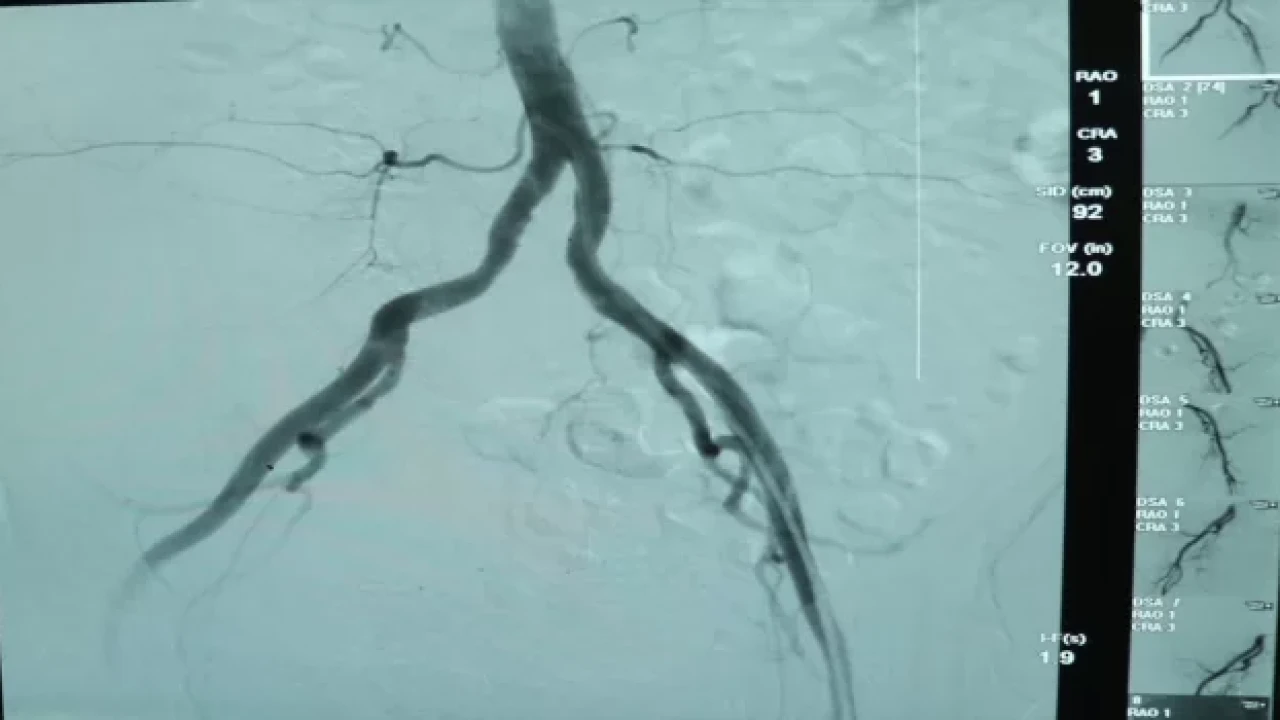

YALOVA (AA) Yalova'da hastaneye kaldırılan ve iç kanaması olan 77 yaşındaki kadın, "anjiyo ile embolizasyon" yöntemiyle tedavi edildi.

Kalp yetmezliği tanısıyla yoğun bakımda tedaviye alınan kadının tetkiklerinde, literatürde az rastlanır bir iç kanaması olduğu belirlendi.

Kanamanın ancak bölgesini tespit edebilen doktorlar, cerrahi müdahale yapılamayacak kadar küçük olan bu alana anjiyo yöntemiyle yaklaşık 4 saatte ulaştı.

Anjiyo ile embolizasyon yöntemi kullanılarak, damar özel bir maddeyle tıkanıp operasyon tamamlandı.

Kardiyoloji Uzmanı Dr. Mehmet Kocaağa, yaptığı açıklamada, tomografi çekiminde karnın arka tarafında yerini bilmedikleri bir damarda kanama gördüklerini söyledi.

Açık cerrahi ile tedavisinin mümkün olamayacağı için anjiyo yöntemini kullandıklarını belirten Kocaağa, "Kanamayı durdurmak işin kolay kısmı ancak tespit etmek zordu. Çünkü saç kadar ince bir damardan kanama oluyordu. Bütün damarları tek tek yakınlaştırıp mikro kateterle görüntüsünü aldık. Bunu tespit etmek yaklaşık 3,5 saatimizi aldı." dedi.

Uzman Dr. Fatih Rıfat Ulusoy ise anjiyo işlemini bu hastada damarı açmak için değil tıkamak amacıyla yaptıklarını kaydetti.

Müdahalenin ardından hastanın iyileşme sürecine girdiğini, bütün değerlerinin normale döndüğünü vurgulayan Ulusoy, "Bu hastamız için cerrahi şansımız yoktu. İlaçla da durduramadık. Tansiyonu düşmeye başlamıştı, şoka giriyordu. Tek çaremiz buydu ve hızlı şekilde görüntülemeyi yaparak kanamayı durdurduk. Hastamızın genel durumu gayet iyi. Sağ kalça kaslarını besleyen bir damar bu. Onun bu şekilde kanaması çok çok düşük bir ihtimal." diye konuştu.